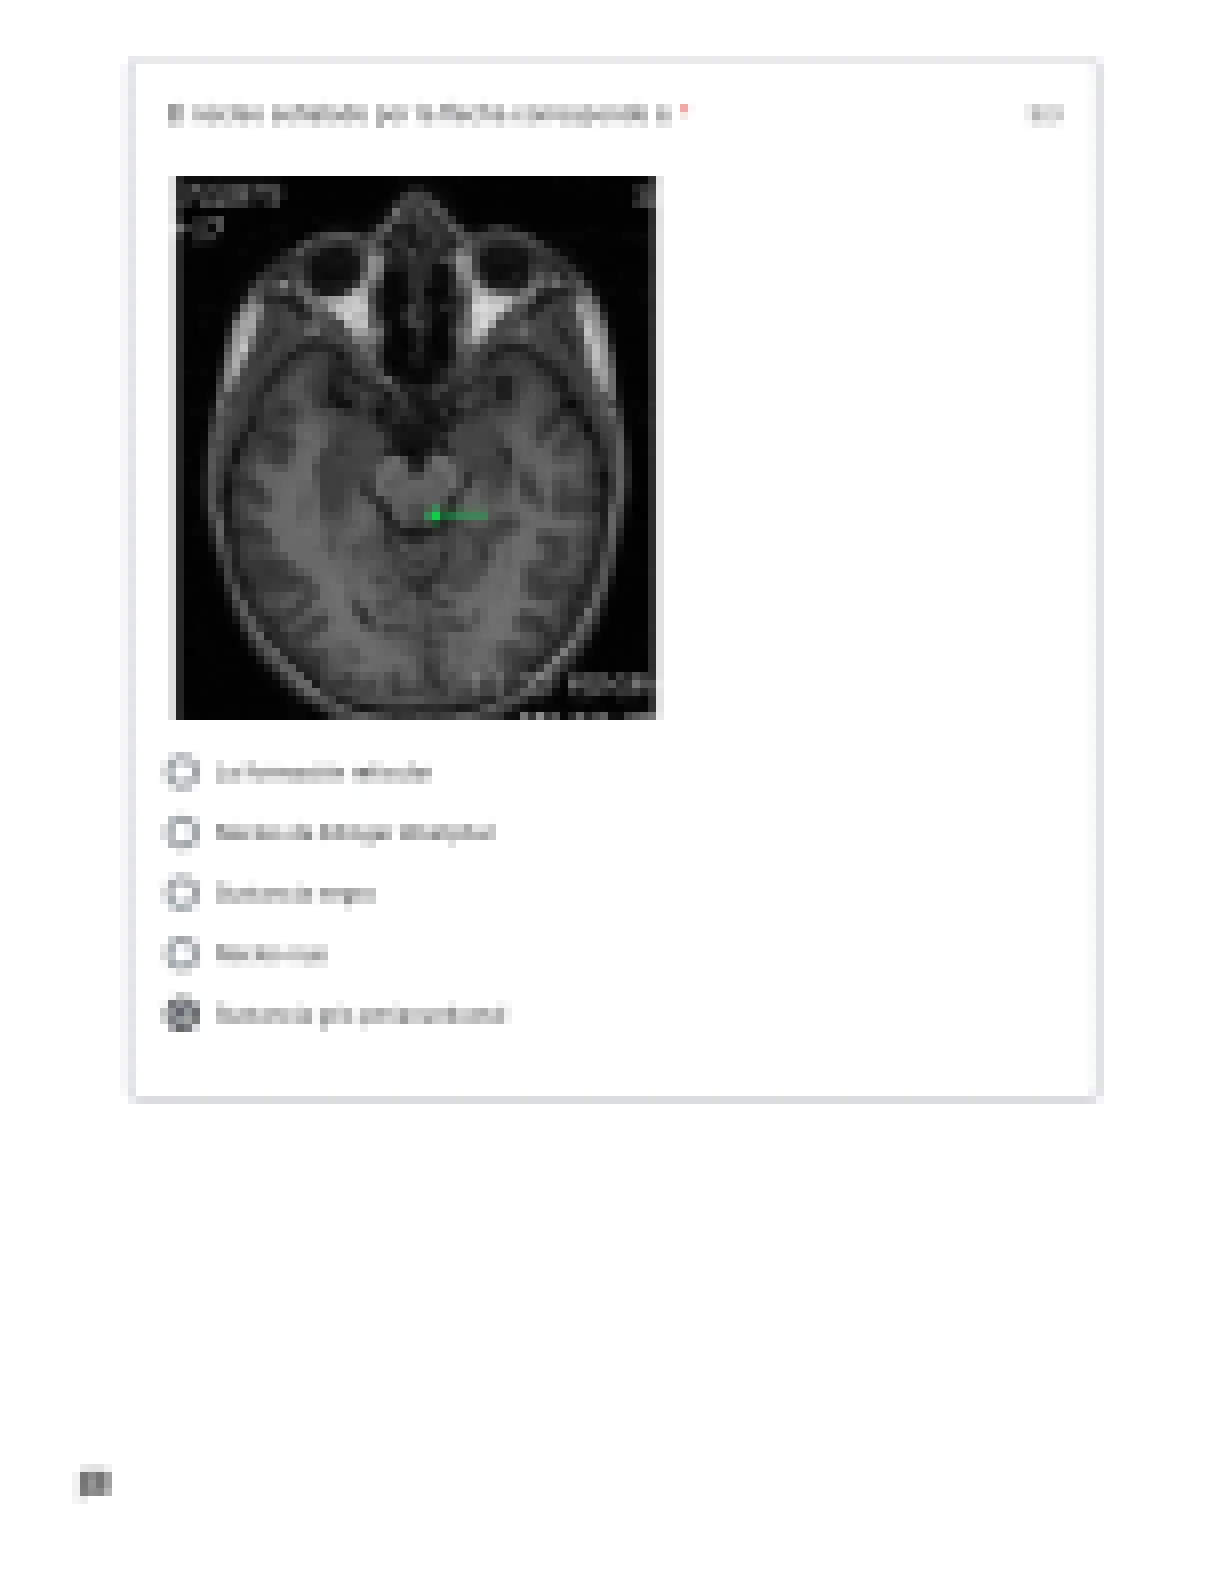

2017979 - ANATOMIA 1

Examen neuroanatomia I